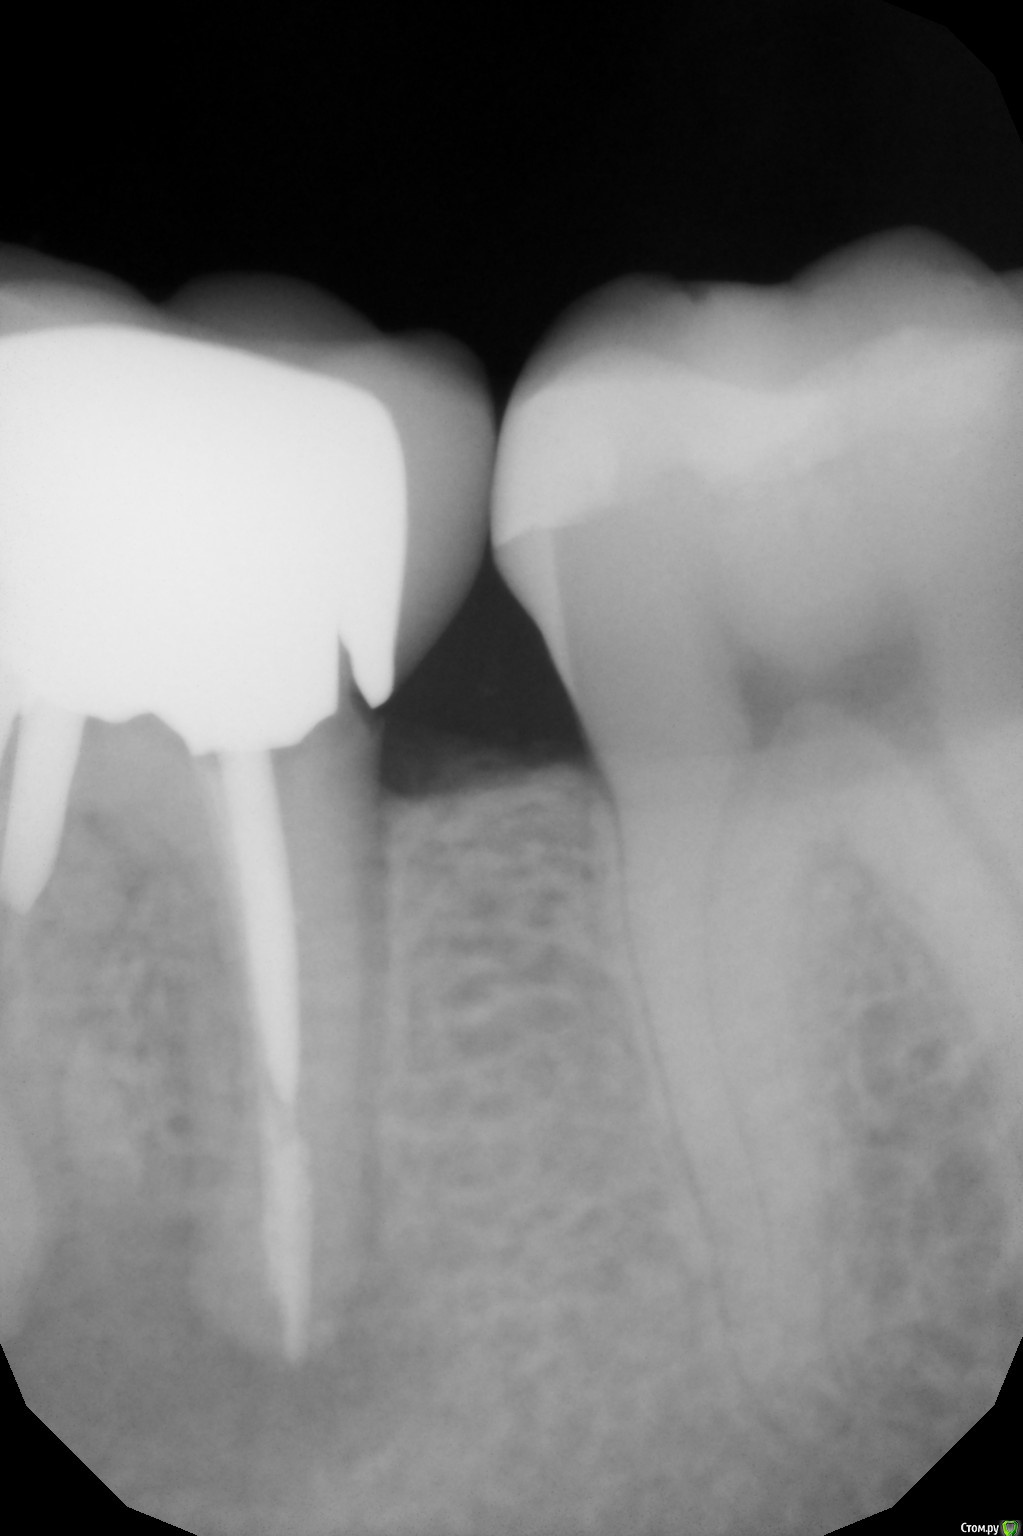

DenisB Опубликовано 15 февраля, 2020 Поделиться Опубликовано 15 февраля, 2020 Здравствуйте! Стал немного побаливать зуб под коронкой, особенно если жевать им твердую пищу (баранки и т.д.). Причем иногда ноющая боль есть, иногда - нет. Коронку на зуб ставили в 2013 году. Сходил к стоматологу, сделали рентген, обнаружили кисту под зубом (см. фото). Стоматолог говорит, что нужно удалять зуб, после этого ставить имплант. Вопрос: возможны ли какие-то другие варианты убрать эту кисту или в данном случае поможет только удаление? Ссылка на комментарий

dima3M Опубликовано 16 февраля, 2020 Поделиться Опубликовано 16 февраля, 2020 Наличие вкладки, большой зоны воспаления и фрагмента инструмента в канале резко снижают прогноз на выздоровление после повторного лечения.Целесообразнее удаление и потом имплантация Ссылка на комментарий